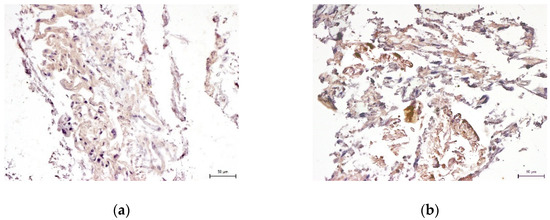

2.3. Differentiation Assay